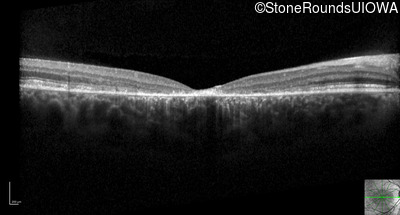

Optical Coherence Tomography - Right - 10/125 -2 sc

Exemplar / OCT Stack

OCT Stack